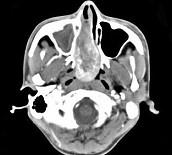

问题 男,20岁,头痛、鼻塞、鼻出血,CT如图所示,最可能诊断为()

选项 A.鼻咽癌 B.巨大的鼻息肉 C.鼻咽纤维血管瘤 D.鼻咽神经纤维瘤 E.鼻咽腺样体增生

答案 C